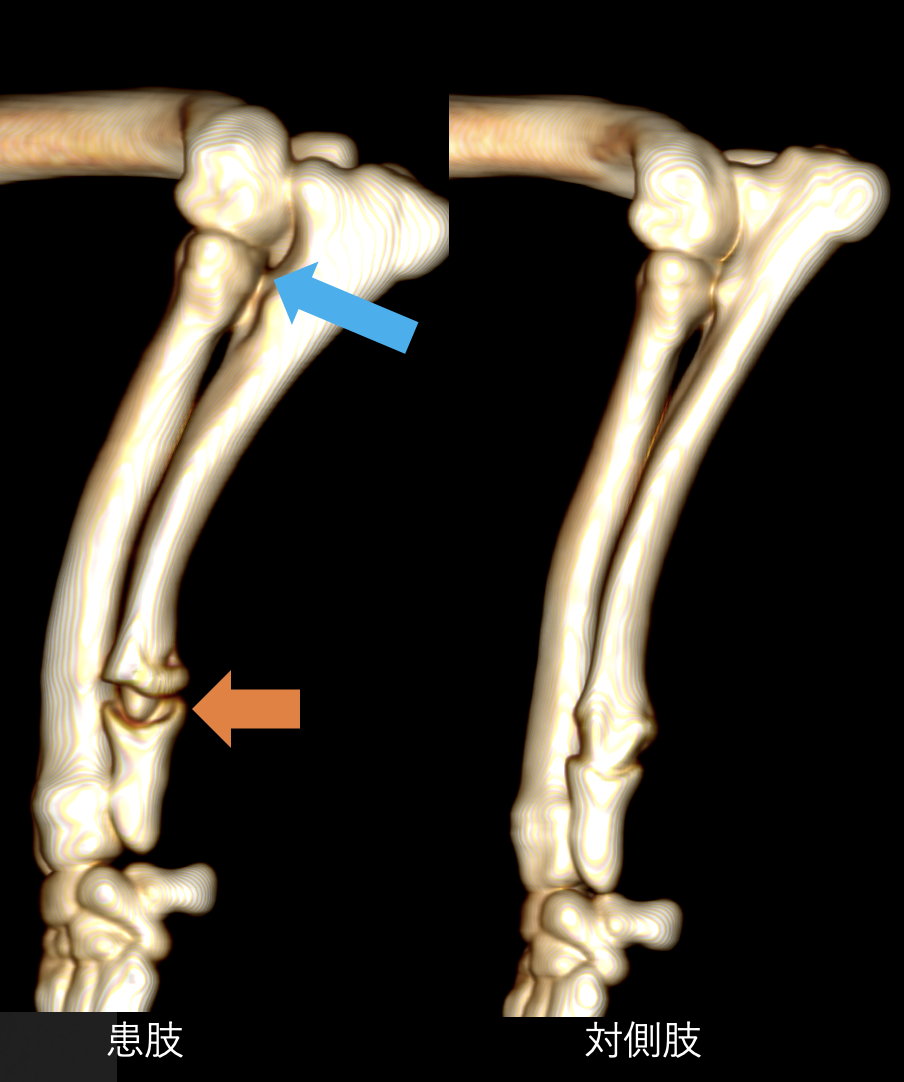

整形外科の雑誌であるVeterinary and Comparative Orthopaedics and Traumatologyに磯野の論文である「Tibial Torsion Malalignment in Small Dogs with Medial Patellar Luxation」が掲載されました。パテラ内方脱臼に対し、脛骨粗面と足根骨の捩れが関与しているをことを示し、その指標の一つを提言した内容になります。ご興味ある方はご覧ください。